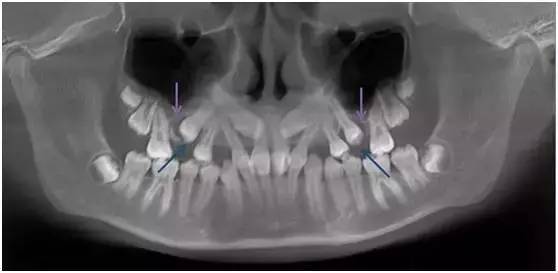

含牙囊肿内充满液体,并且随着时间的推移会逐渐增大,造成进展式骨破坏及损伤邻牙牙根(如图蓝色箭头处)。牙根受损的牙齿越到后期,往往难以治疗,甚至不得不拔除。

图:左上中切牙及尖牙的含牙囊肿

造成骨质缺失, 左上侧切牙牙根吸收

所以一旦发现含牙囊肿要及时手术刮除,并尽快将牙齿牵引助萌,避免囊肿复发。